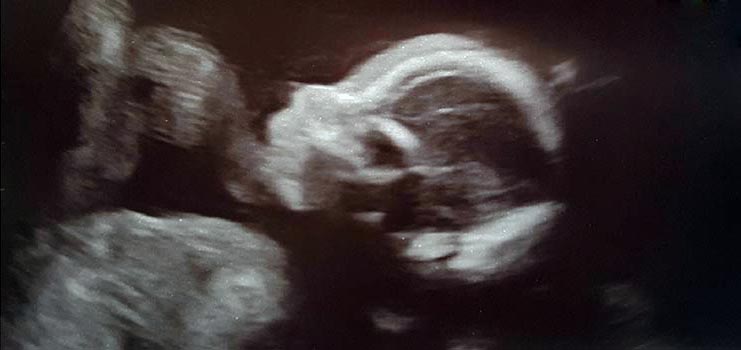

Und es wird ein .... - Tagebücher aus der Schwangerschaft von Leandra aus Lübeck

Eine neue wunderbare, aufregende und vielleicht auch lang erwartete Lebenszeit beginnt. Für unsere Tagebücher-Blogs haben wir immer 3-4 schwangere Frauen in unterschiedlicher Schwangerschaftsphase, die in freudiger Erwartung über jede Woche dieser spannenden Zeit schreiben, uns und die vielen tausend Follower:innen daran teilhaben lassen und damit unvergessliche Momente schaffen.